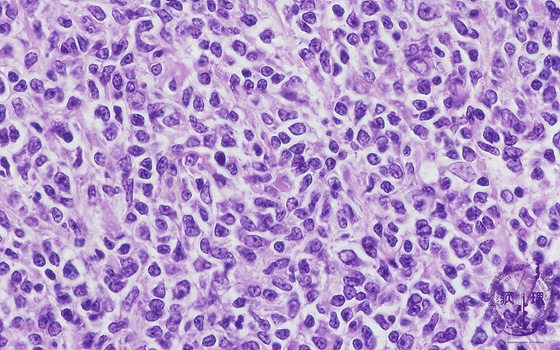

- ★(5)Follicular lymphoma

Microscopic image (H&E high power view): Nuclei of neoplastic lymphocytes are larger than those of mature lymphocytes (arrow No.1), but smaller than those of histiocytes. Some of the smaller tumor cells are called cleaved cells because their nuclei have irregular, notched borders (arrow No.2). Admixed centroblasts (arrow No.3) are larger tumor cells with prominent large nucleoli. The germinal center growth pattern is relatively monotonous in contrast to the heterologous appearance seen in non-neoplastic, reactive areas.